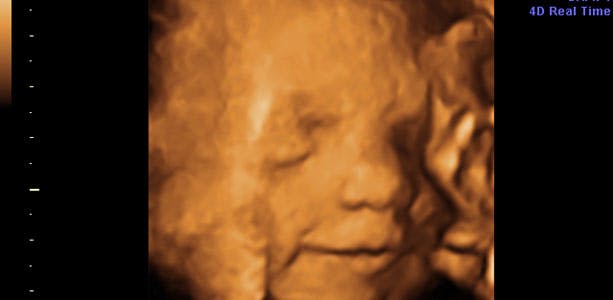

Gravid uge 26: Åbner og lukker øjnene

Hjernen udvikler sig hurtigt nu, og hjernebarken begynder at få de karakteristiske furer. Baby træner øjenmuskulaturen ved at åbne og lukke øjnene. Det ved man fra kikkertundersøgelser inde i livmoderen, hvor det er observeret, at baby tager hænderne op foran øjnene, når lyset rammer det. I slutningen af ugen måler barnet cirka 32 centimeter og vejer omkring 900 gram. Lårbensknoglen måler cirka 4,6 centimeter og maven omkring 22 centimeter.